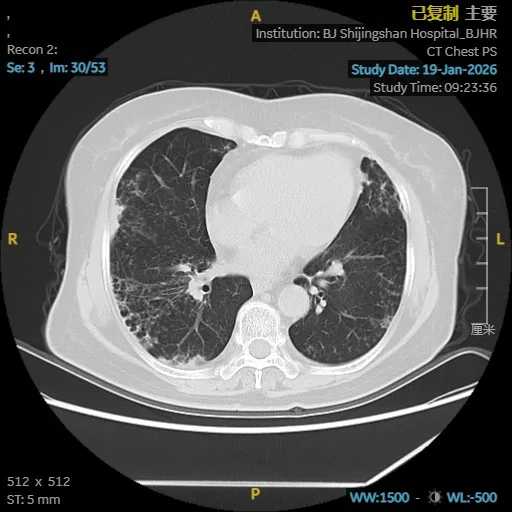

依托医院高清CT、肺功能、气管镜及精准分子检测平台,团队很快锁定了隐藏在表象背后的真实病因:鸟胞内分枝杆菌合并耐药念珠菌感染,同时伴有进展性肺间质纤维化。这两种疾病相互交织,诊治难度大,对医疗团队提出了很高要求。

为给患者制定最安全有效的治疗方案,马霞主任医师立即启动MDT机制,联合临床药师、影像科、检验科专家进行会诊。在多学科共同研判下,团队为栗女士量身定制了集抗感染、抗真菌、抗纤维化于一体的综合治疗策略,在精准打击病原的同时,全力保护肺功能。